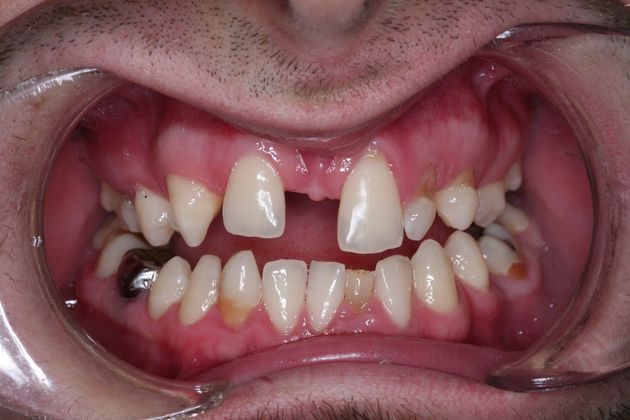

Full mouth rehabilitation. This 20 year old patient had emigrated from Bosnia only a few years earlier with his mother and two sisters after his father had perished in the Bosnian/Serbian conflict. He had severe hereditary dental dysplasia, with multiple retained baby teeth where permanent teeth never formed. He had a total of nine missing teeth, and the teeth that were present were not in their correct positions, leading to a poor bite relationship and multiple large gaps throughout his mouth. He was embarrassed to smile and wanted to know what could be done. His was a very complex case requiring Smile design and; the services of an oral surgeon to take out the baby teeth and strategically place implants at different times of his treatment, an orthodontist to level, straighten and create the proper size spaces for the placement of nine implants, gum sculpting, whitening, and the placement of fillings and crowns on natural teeth, and crowns on the nine implants. It took some time, but he got a great result and the resulting confidence has helped him go to college, get a better job and have a social life! Procedures: Smile design, oral surgery and implant placement, orthodontics, gum lift, whitening, fillings and crowns. TESTIMONIAL:" Dr. Balloch is a very skilled, compassionate and empathetic dentist who develops a personal relationship with his patients. He is (by far) the best dentist that I have experienced in my 85 years. His dental and office staff are equally friendly and professional. Dr.Balloch definitely exceeded my expectations. I highly recommend!"